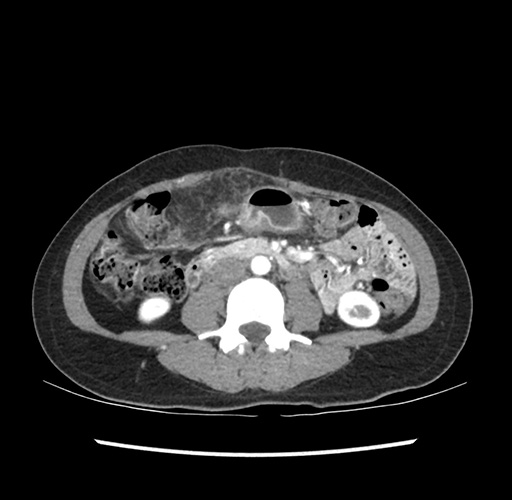

Imaging Analysis

Look through the patient's CT scan to identify any areas of concern for the necessary procedure.

Based on your CT findings, which issue(s) would give reason for "planned slowing down moment(s)" in this case?

Considering a standard left lateral sectionectomy procedure, what step(s) of the operation would you do differently in this case ?